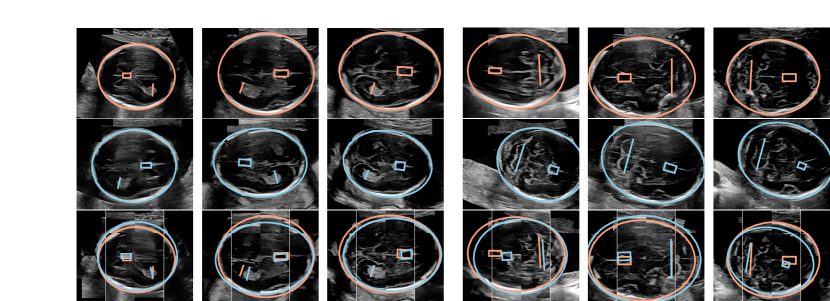

| Target image |

| Source image |

| Aligned images |

| TV |

| TC |

Application to Image Registration. After assigning the anatomical structures to the corresponding cluster labels, 88.0% of the discovered landmarks were near the correct annotated structure (within a radius of 10% of the HC long axis). Conversely, 77.1% of the annotated structures were near a corresponding discovered landmark. Alignment was performed for 89 (62%) TV images and 67 (54%) TC images which had all annotated structures correctly identified. Fig. 3 shows exemplary results and Table 1 shows the corresponding quantitative evaluation. The alignment errors are consistently lower for salient landmarks compared to the baselines.

For image registration, the results show that our approach can achieve good alignment without explicit supervision. The landmarks are successfully matched based on the local features of the saliency prediction CNN. The intensity-based registration performs significantly worse and only slightly above the trivial “No align” and “Flip” baselines since intensity-based alignment of ultrasound images is inherently difficult due to noise, shadowing, artifacts and the visibility of maternal anatomies [12]. The landmark discovery based on visual saliency prediction effectively ignores the irrelevant structures as a human would. A limitation is that landmark-based alignment is only possible if all necessary landmarks are detected. Moreover, the quality of alignment may be limited by the affine transform, as visible for the TC plane in Fig. 3, and a non-rigid transformation might yield an improvement.